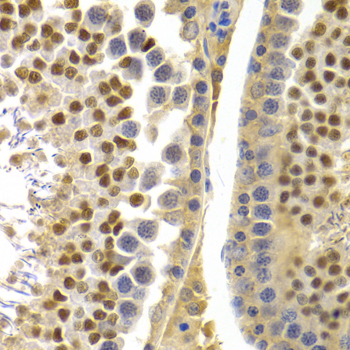

Immunohistochemistry of paraffin-embedded rat testis using APOBEC3G at dilution of 1:100 (40x lens).